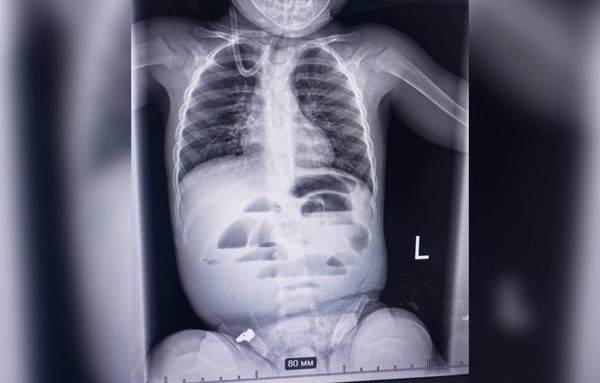

Малюк у віці 1 рік і 8 місяців проковтнув гідрогелеву кульку.

Фото: Регіональний медичний центр родинного здоров'я

Малюка доставили до лікарні з підозрою на кишкову непрохідність. Проведене рентгенологічне обстеження показало характерні ознаки цього стану. Команда лікарів різних спеціальностей ухвалила рішення про термінову операцію.

Під час операції виявили стороннє тіло, що повністю перекривало просвіт кишечника. Ним виявилася гідрогелева кулька діаметром до 3 см.